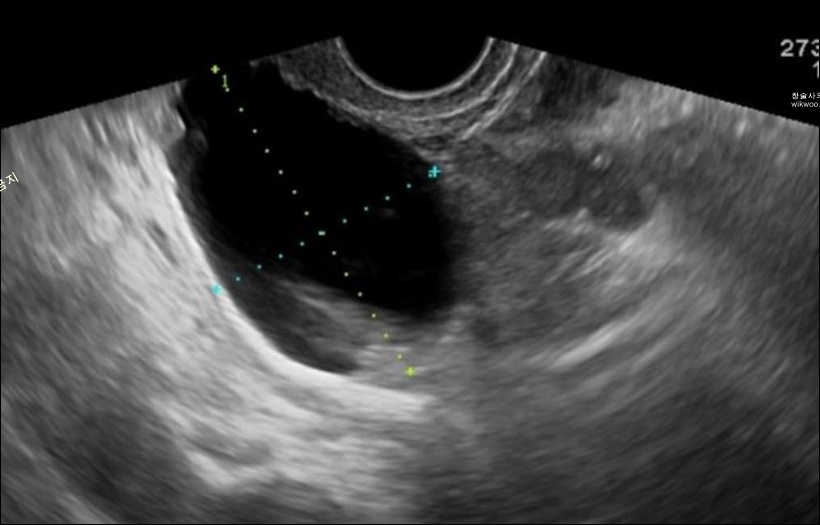

난소는 자궁의 양 옆에 위치하여 배란을 통한 생식 기능과 함께 여성호르몬을 분비하는 기관입니다. 이러한 난소에 혹이 생기는 질환을 난소낭종 또는 난소물혹이라 하며 가임기 여성중 3~4명이 겪을 정도로 발병률이 높습니다.

난소에 생기는 물혹의 크기는 작기는 몇 밀리미터부터 7cm까지 다양합니다. 다행스러운 것은 물혹의 99% 이상이 양성이기 때문에 큰 이상은 발생하지 않는다는 것입니다.

물혹의 크기가 2cm~3cm 이내라면 짧게는 수주에서 수개월 이내에 자연적으로 소실하는 경우가 많기 때문에 초음파 검사를 통해 물혹이 사라지는지 확인하면서 경과를 관찰합니다.

난소낭종으로 진단을 받으면 물혹의 크기를 알려주는데 2cm, 3cm, 4cm, 5cm까지는 위의 조건을 동반하지 않는 경우에는 꼭 수술을 해야 하는 것은 아니라고 합니다.

단 4cm 이상의 낭종은 몇 달간 초음파를 통해 유심히 지켜볼 필요가 있습니다.

※ 병원 의료진 소견에 따라 낭종 크기가 6cm, 7cm, 8cm인 경우에도 당장 복강경 수술을 권장하지 않고 추적 관찰하자고 하는 경우도 있습니다. 물혹은 배란으로 인해 커졌다가 작아졌다가 할 수 있습니다. 따라서 초음파 당시 발견된 물혹 크기만으로 바로 수술을 권하는 것은 신중할 필요가 있습니다.